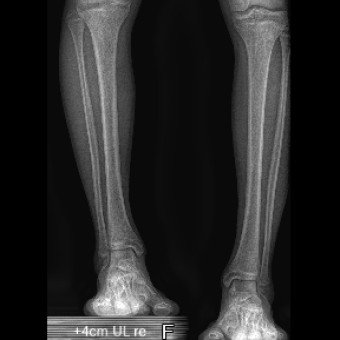

Die Knochenverlängerung mit dem magnetgetriebenen Marknagel Precice® hat sich als bedeutendste technologische Innovation in der Extremitätenrekonstruktion etabliert. Bei dieser Methode wird der getrennte Knochen durch Callusdistraktion täglich um etwa 1 mm verlängert. Im Vergleich zu externen Fixateuren ist diese vollimplantierte Lösung für Patientinnen und Patienten deutlich angenehmer und weniger schmerzhaft.

Die Ergebnisse sind ausgezeichnet und Komplikationen selten. Im schweizerischen Vergleich gehören wir auf diesem Gebiet zu den führenden Kliniken.